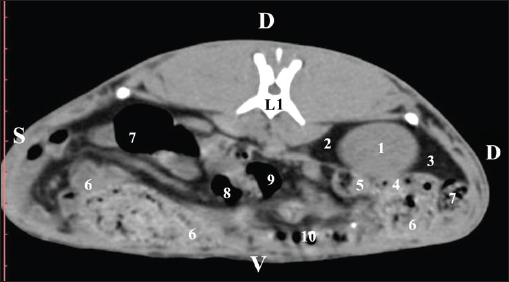

At the next scan level (L1), the normoattenuated image of the right kidney was more detailed and in contact with the lobus hepatis dexter, lobus caudatus, duodenal pars descendens, and ileum. The cortex renis and medulla renis were not clearly differentiated. Pelvis renalis appeared as a linear hypoattenuated finding against the relatively normoattenuated kidney cortex and medulla. The proximal part of the ureter was seen medial to the right kidney (Figs. 2 and 3).

Fig. 2. Pre-contrast computed tomography (CT) anatomical scan of the regio abdominis cranialis at the L1 level. (1) Ren dexter; (2) lobus hepatis dexter; (3) lobus caudatus (proc. caudatus) with visceral adipose tissue; (4) pars descendens of the duodenum; (5) ileum; (6) cecum; (7) colon ascendens; (8) colon transversum; (9) colon descendens; (10) jejunum.

Fig. 3. Pre-contrast computed tomography (CT) anatomical scan of regio abdominis cranialis at the L1 level. (1) Medulla renis; (2) cortex renis; (3) pelvis renalis; (4) lobus caudatus (proc. caudatus) with visceral adipose tissue; (5) ureter; (6) pars descendens of the duodenum; (7) jejunum; (8) cecum; (9) colon ascendens; (10) lien; (11) colon descendens; (12) colon transversum.